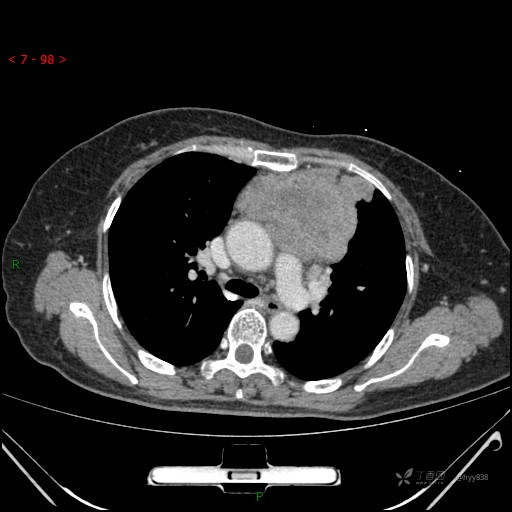

辅助检查:CT

动脉期

静脉期